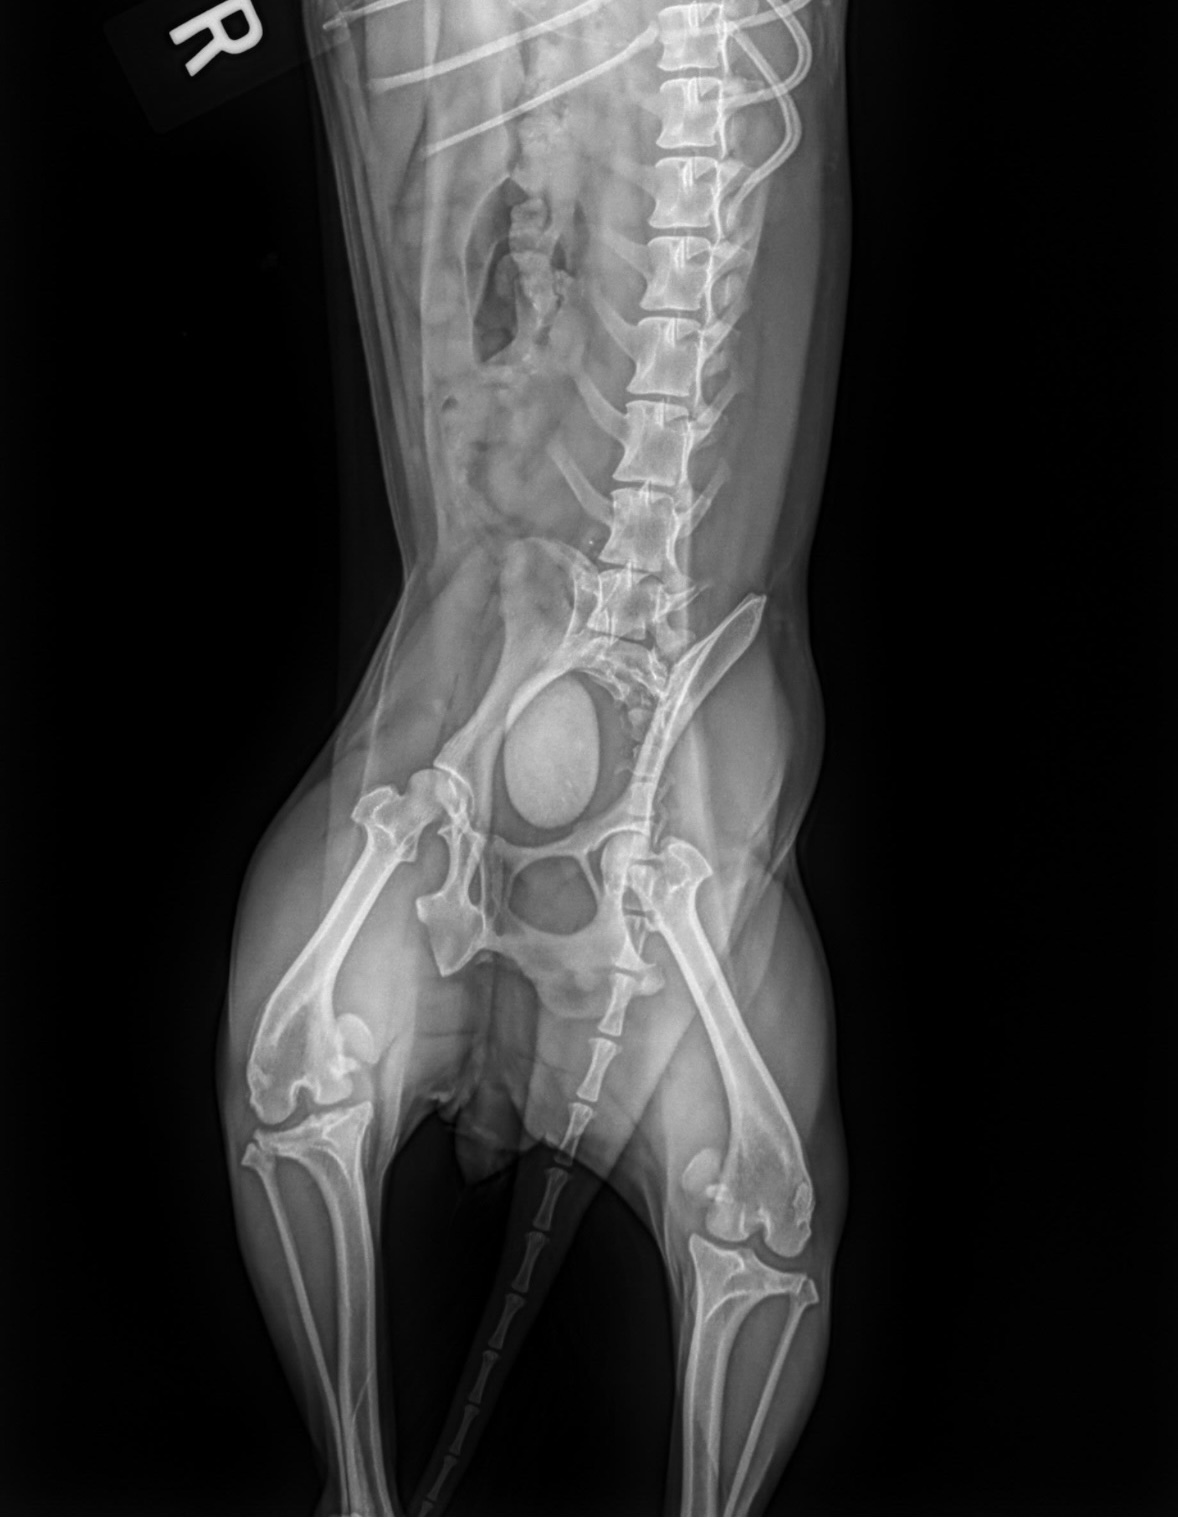

An X-ray revealed what appeared to be a hardened bladder wall and Stage 4 luxating patellas — also known as permanently dislocated kneecaps.

Once under anesthesia, they discovered she had undergone bladder surgery in the past. And that “hardened wall” on the X-ray?

It wasn’t a wall at all.

It was a massive bladder stone filling her bladder.